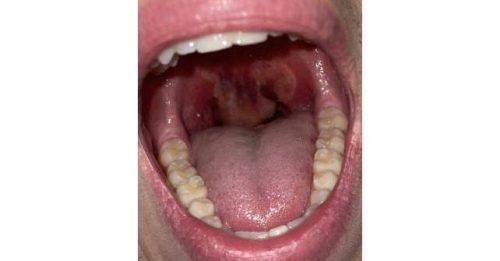

Case Report: Uvular Edema in a Marijuana Smoker

November 5, 2024 - Meghana Keswani, MD; M. Kathryn Mutter, MD, MPH; and Moira E. Smith, MD, MPH - 0 Comment

A healthy 20-year-old male presented with one day of a progressively worsening sore throat with difficulty swallowing,…